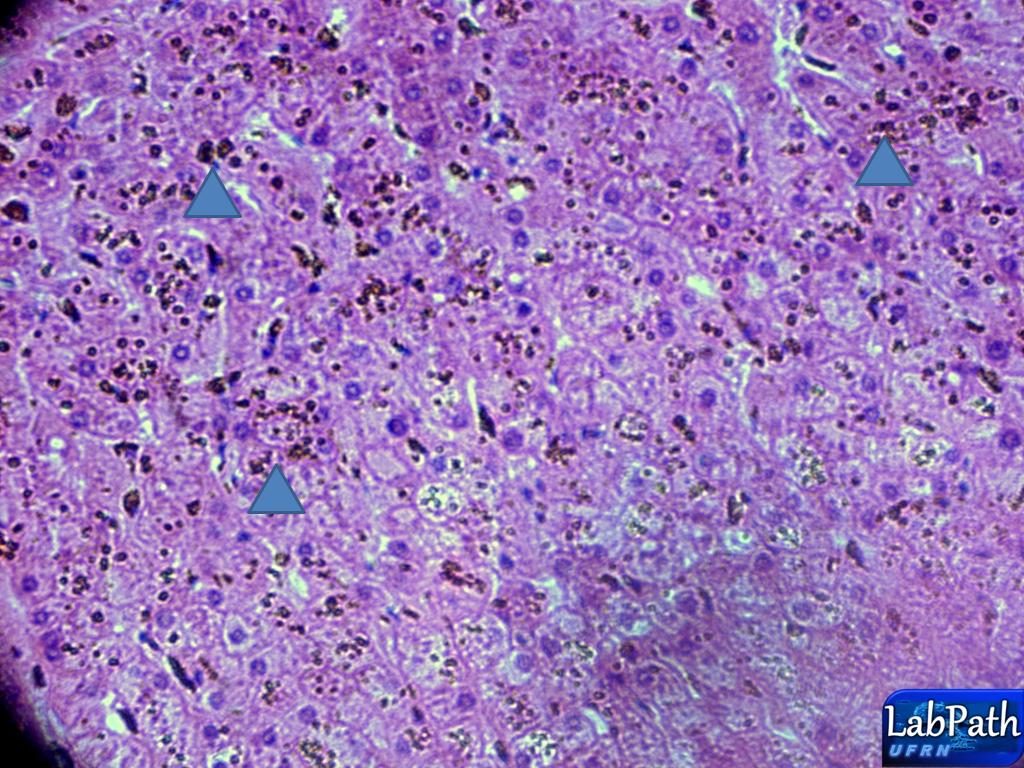

40x

No aumento maior,nota-se a grande quantidade de hemossiderina no parênquima hepático(podendo-se notar pelo fato de se observar sua refringência ao mexer no micrometro) (cabeças de seta azul).

Translation: In larger increase, there is a large amount of hemosiderin in the liver parenchyma (can be noted by the fact of observing their refringence to move in micrometer) (blue arrowheads).